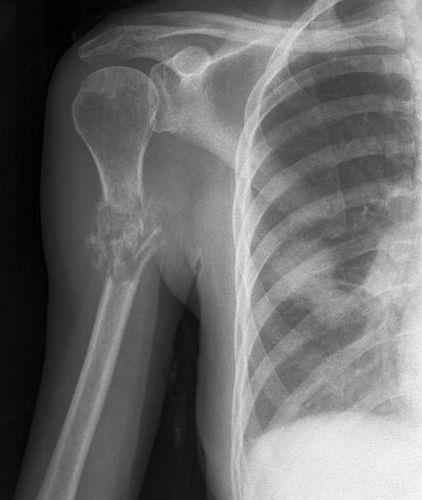

골 용해성 병변(Osteolytic)이 관찰된다면 : 신장암, 갑상선암, 위, 대장암 을 생각해 보아야 합니다.

조골성 병변(Osteoblastic)이 관찰된다면 : 전립선암, 방광암, 자궁암 을 생각해 보아야 하며

혼합성 병변이 관찰된다면 : 유방암 을 생각해보아야 합니다.

상지의 골병변은 폐암과 유방암일 확률이 높습니다.

전이성 골종양의 경우 영상과 같이 치료가 무척 어렵습니다. 지푸라기라도 잡는 마음으로 방사선치료와 항암화학요법을 할 수 있습니다. 5년 생존율이 높아 보이는 환자군에서 장관골과 골반골의 임박 골절, 병적 골절 에는 예방적 고정술을 해볼 수 있습니다. (RT에도 효과가 없고, 2.5cm 정도로 큰 사이즈와 cortex가 50%이상 파괴되어 부러지기 직전일때, 소전자의 견열골절이 있을때 = Mirel 8점이상)